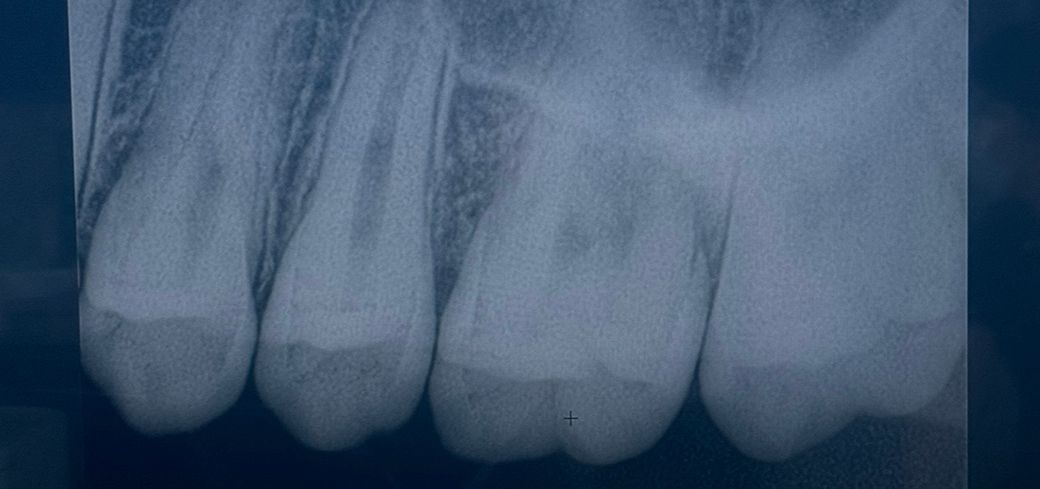

25~26 치아고 첫번째, 세번째 사진이 최근 두번째 사진이 올해 2월 입니다 인접면 충치가 맞는지 얼마나 진행되었는지 궁금합니다

25~26 치아고 첫번째, 세번째 사진이 최근 두번째 사진이 올해 2월 입니다 인접면 충치가 맞는지 얼마나 진행되었는지 궁금합니다 -> 25,26 사이 인접면 충치 크게 문제 없어 보입니다

사진으로 봤을 경우에는 인접면에 어두운 면이 보입니다. 충칠 가능성이 높지만 정확한 확인은 육안으로 확인을 해봐야 알 수 있을것으로 생각됩니다.

자세한 확인을 위해서 치과에서 진료를 받아보는 것을 권유드립니다.